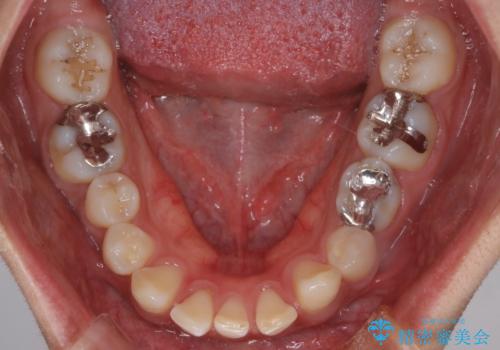

【インビザライン】空隙歯列の矯正

- 前歯の隙間を主訴に来院されました。

なるべく目立たない治療を希望されましたので、インビザラインにて治療を行なっております。

単純に前歯の隙間の閉鎖をしてしまうと、前歯に早期接触が生まれ、臼歯が噛まなくなってしまいます。適切な治療計画を立てることで、噛み合わせも良好な結果を得ることができました。